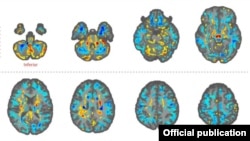

Las imágenes revelaron “diferencias significativas en el volumen de materia blanca cerebral total, [en] volúmenes locales de materia blanca y gris”, y en la integridad microestructural del tejido del cerebelo. También mostraron diferencias de “conectividad en las subredes auditivas y visoespaciales, pero no en la subred de control ejecutivo”.

“Lo que pueden decirnos las imágenes cerebrales [de resonancia magnética] es si le pasó algo al cerebro”, le dijo a The New York Times la doctora Ragini Verma, profesora de Radiología de la Universidad de Pensilvania y la encargada del estudio. “Y la respuesta es que sí […], pero no sé la causa. Las imágenes por sí mismas no pueden decirnos eso”.